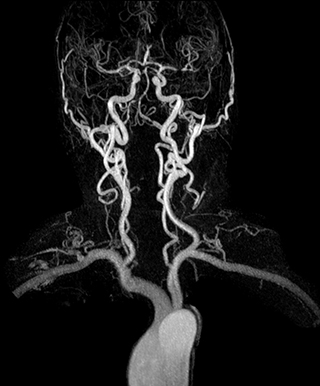

“In our peripheral MRA run-off studies with Ambition we realize key benefits, including outstanding image quality and significantly reduced breath-hold and scan times, which not only benefit the patient, but also provide the opportunity to add sequences that could aid in diagnosis,” Dr. Peña says.

“Before we had Ingenia Ambition, our CE-MRA run-off studies would first acquire a dynamic pre-contrast scan with 20-25-second breath-holds, then inject the contrast, do another acquisition and then subtract the two,” says Avila. “Now, mDIXON XD allows us to complete the study in just one single pass – without need for a pre-exam – which eliminates subtraction artifacts and almost halves the scan time. In addition, mDIXON provides much better background suppression, which really improves vesselto-background contrast. And, thanks to Compressed SENSE, the single breath-hold is not long and we improve image resolution.”

The subtractionless peripheral MR angiography shows improved vessel-to-background contrast and high resolution. Ingenia Ambition 1.5T.

The time saved by Compressed SENSE and mDIXON XD is sometimes used to include additional sequences. An example are peripheral MRA studies, in which Compressed SENSE and mDIXON XD help achieve a 5- to 10-minute reduction in scanning time. This brings the total time down, from the 45 minutes needed with their previous system to about 30 to 35 minutes on Ingenia Ambition, thus providing ample time to include additional sequences.

“These scans are so fast now that we have been able to add a non-contrast MRA sequence within the same timeslot. We compare the respective image quality with the goal to determine whether the non-contrast sequence could be an alternative for patients who can’t tolerate gadolinium contrast agents due to poor kidney function,” says Avila. “We find the image quality of the non-contrast sequence so good that we can now also offer peripheral MRA to these patients whom we had been unable to serve before Ambition, so that has been great.”